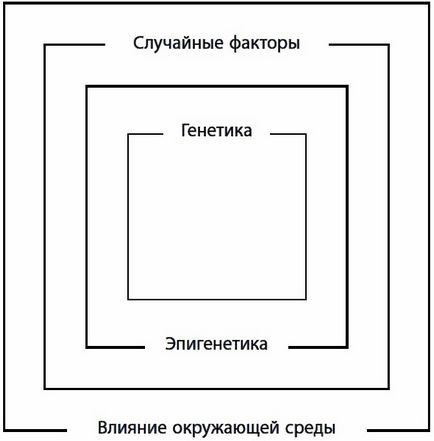

Якщо міркувати філософськи, у старіння дійсно одна причина: недосконалість пристрої живого організму. Згідно з ідеєю професора Гарвардської школи медицини Вадима Гладишева, деяка кількість помилок в роботі живих систем долає всі захисні бар'єри, накопичується і викликає старіння. Єдиний спосіб уповільнити старіння, як він вважає, - уповільнити наш метаболізм. Пітерський вчений Олексій Голубєв дотримується подібних поглядів: в тканинах при обміні речовин постійно відбуваються побічні реакції, в результаті акумулюються помилки метаболізму, що призводять до старіння.

Однак «недосконалість» - занадто загальна причина. Більш конкретні фактори старіння умовно можна розділити на чотири великі групи (рис. 3): це гени, в тому стані, в якому вони нам дісталися у спадок (генетика); це рівень активності генів в кожній тканини (епігенетика); це діючі на нас фактори навколишнього середовища - їжа, клімат, якість повітря і води; і, нарешті, наше старіння додатково визначається випадковими збоями. В результаті дії цих причин відбувається відхилення живої системи від оптимального режиму функціонування, тобто порушення гомеостазу. Вченим відомо безліч видів таких відхилень: це і окислювальні реакції під впливом вільних радикалів, і розриви хімічних зв'язків під дією води, і порушення структури різних молекул під впливом тепла і хімічних речовин (наприклад, шкідливе взаємодія білків і глюкози), їх пошкодження іонізуючоїрадіацією і ультрафіолетом і злипання деяких білків з утворенням внутрішньоклітинного і позаклітинного сміття, і нестача деяких речовин, збої в регуляції фізіологічних процесів і невиправлених в ДНК ... Мн ожество маленьких, але дуже шкідливих випадковостей, накладаючись один на одного, поступово підточують наше здоров'я. Системи підтримання сталості внутрішнього середовища (гомеостазу) самі згодом розхитуються, тому з віком фізіологічні функції все далі відхиляються від оптимуму. Якщо гомеостаз не відновлено, виникає патологічний процес, який збільшує ризик загибелі організму. Саме такі патологічні процеси ми називаємо вік-залежними хворобами.